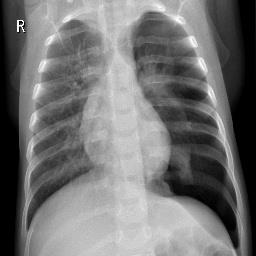

Pneumonia, a respiratory infection brought on by bacteria or viruses, affects a large number of people, especially in developing and impoverished countries where high levels of pollution, unclean living conditions, and overcrowding are frequently observed, along with insufficient medical infrastructure. Pleural effusion, a condition in which fluids fill the lung and complicate breathing, is brought on by pneumonia. Early detection of pneumonia is essential for ensuring curative care and boosting survival rates. The approach most usually used to diagnose pneumonia is chest X-ray imaging. The purpose of this work is to develop a method for the automatic diagnosis of bacterial and viral pneumonia in digital x-ray pictures. This article first presents the authors' technique, and then gives a comprehensive report on recent developments in the field of reliable diagnosis of pneumonia. In this study, here tuned a state-of-the-art deep convolutional neural network to classify plant diseases based on images and tested its performance. Deep learning architecture is compared empirically. VGG19, ResNet with 152v2, Resnext101, Seresnet152, Mobilenettv2, and DenseNet with 201 layers are among the architectures tested. Experiment data consists of two groups, sick and healthy X-ray pictures. To take appropriate action against plant diseases as soon as possible, rapid disease identification models are preferred. DenseNet201 has shown no overfitting or performance degradation in our experiments, and its accuracy tends to increase as the number of epochs increases. Further, DenseNet201 achieves state-of-the-art performance with a significantly a smaller number of parameters and within a reasonable computing time. This architecture outperforms the competition in terms of testing accuracy, scoring 95%. Each architecture was trained using Keras, using Theano as the backend.